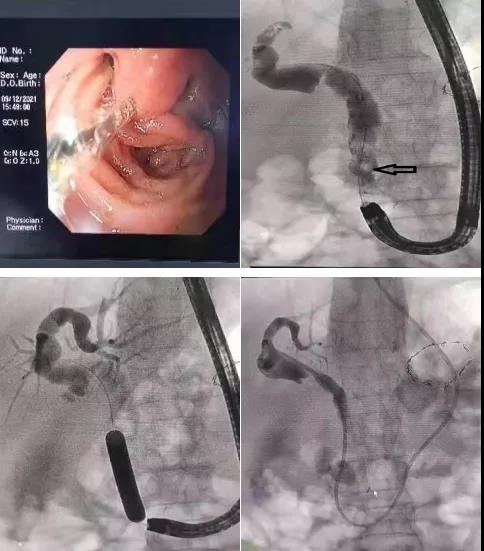

近日,消化內(nèi)二科成功開展首例畢Ⅱ式胃大部切除術(shù)后復(fù)發(fā)難治性膽總管結(jié)石的ERCP取石手術(shù)。

患者81歲高齡女性,既往胃大部切除畢Ⅱ式吻合術(shù)后30余年,因發(fā)熱、腹痛入院,診斷為膽總管結(jié)石、急性梗阻性化膿性膽管炎。患者存在高齡、感染性休克等情況,病情復(fù)雜危重,蓋偉主任立即爭分奪秒組織科內(nèi)專家仔細(xì)分析討論病情,決定首選ERCP取石術(shù)。

與家屬充分溝通后,蓋偉主任和田宗彪主治醫(yī)師開始內(nèi)鏡下取石術(shù),交替使用十二指腸鏡和胃鏡找到改道后的十二指腸乳頭,通過胃鏡完成插管、乳頭擴(kuò)張成型、取石及鼻膽管置入,順利完成手術(shù)。術(shù)后,患者腹痛、發(fā)熱、黃疸等癥狀消失,三天后順利出院。

畢II式術(shù)后患者行ERCP與一般普通患者相比,手術(shù)難度很大,要求術(shù)者有極高的技術(shù)水平及經(jīng)驗(yàn)。它的主要難點(diǎn)有:1.吻合口岔路口的抉擇。由于消化道重建后輸入袢、輸出袢辨別極為困難,輸入袢太長,內(nèi)鏡無法到達(dá)十二指腸乳頭,如果錯誤地選擇了輸出袢的方向進(jìn)鏡,將不可能找到目標(biāo)。2.內(nèi)鏡行走方向相反,操作反?;?。常規(guī)內(nèi)鏡操作從胃到十二指腸降段乳頭,自上而下,順勢而行;而畢II式吻合術(shù)后卻要逆流而上。術(shù)者操作極不順手,且腸道反折處內(nèi)鏡通過困難,很容易造成腸道穿孔。3.采用胃鏡而非十二指腸鏡取石操作難度系數(shù)成倍增加。以上原因?qū)е略擃惢颊逧RCP成功率僅有普通人群的三分之一,此類患者若行常規(guī)治療轉(zhuǎn)外科行開腹手術(shù),創(chuàng)傷大,愈合慢,對患者身體各項(xiàng)指標(biāo)要求高,術(shù)后容易并發(fā)其他膽道疾病。且該患者高齡,基礎(chǔ)疾病較多,外科手術(shù)風(fēng)險(xiǎn)更大。采用內(nèi)鏡下取石則創(chuàng)傷小、手術(shù)時間短、術(shù)后恢復(fù)快、住院時間短。